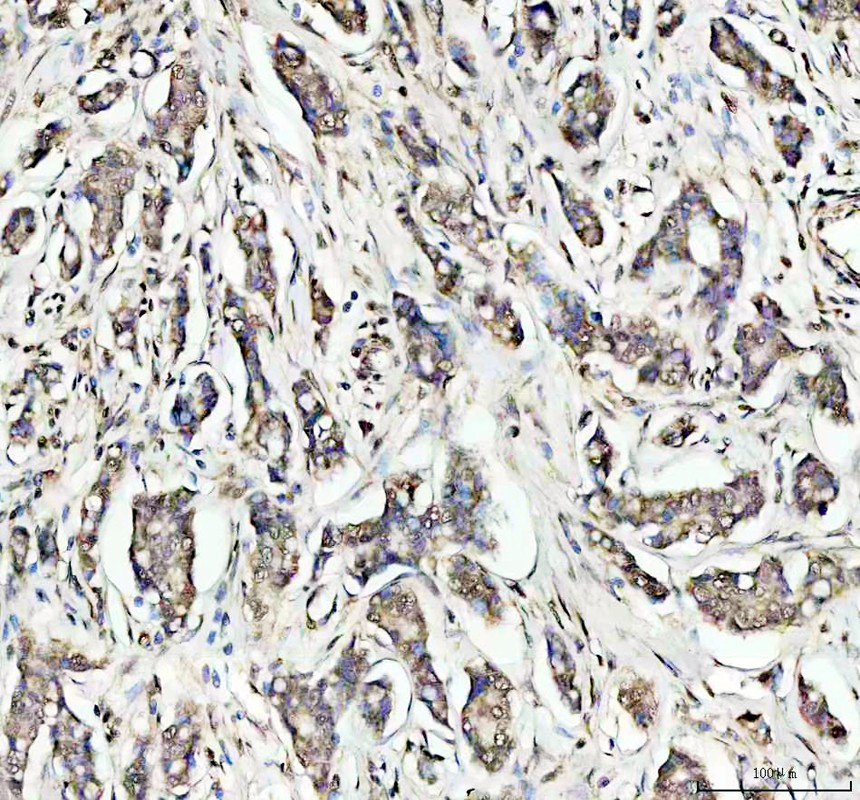

IHC analysis of OGG1 using anti-OGG1 antibody (A00768-1).

OGG1 was detected in a paraffin-embedded section of human lung cancer tissue. The tissue section was incubated with rabbit anti-OGG1 Antibody (A00768-1) at a dilution of 1:200 and developed using HRP Conjugated Rabbit IgG Super Vision Assay Kit (Catalog # SV0002) with DAB (Catalog # AR1027) as the chromogen.